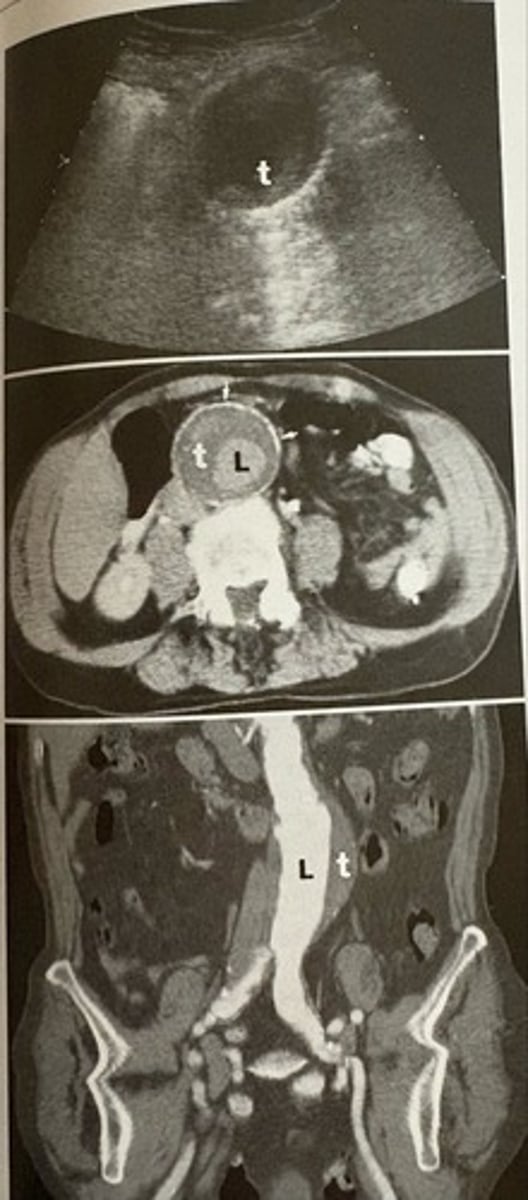

fusiform aneurysm

what pathology is present?